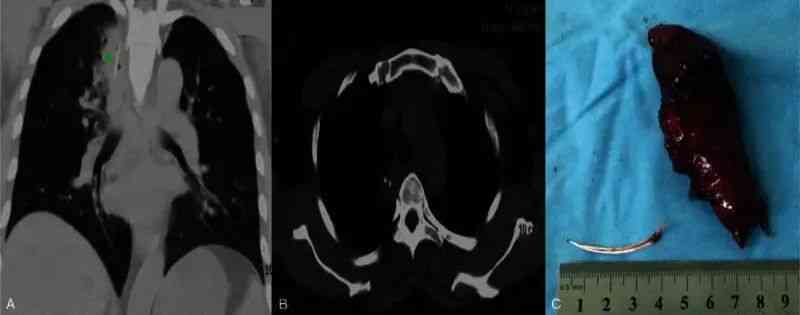

在极少数情况下,鱼刺甚至可能因为反复的错误尝试穿透食管进入胸腔或肺部。一例病例报道显示,患者在误吞鱼刺后出现肺部脓肿,最终需要胸腔镜手术取出异物[5]。